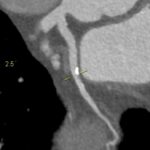

Figururile 1-9: reconstrucție în axul lung al vasului pentru arterele coronare cu evidențierea unui calibru global crescut la nivelul acestora și cu încărcătură ușoară-moderată de placă în principal calcificată

Discuţie caz nr 132: Examinările coroCT se efectuează în principal pentru aprecierea încărcăturii de placă precum și pentru evidențierea reducerilor de lumen ce necesită tratament. Această examinare a evidențiat creștere globală a calibrului arterelor coronare și o încărcătură ușoară-moderată cu placă în principal calcificată, fără a se evidenția arii de stenoză.

DE LUAT ACASĂ!!! Ectazia coronariană este o afecțiune rară caracterizată prin dilatarea anormală (diametrul vasului este de 1.5 ori mai mare) a arterelor coronare, care poate duce la afectarea fluxului sanguin și la un risc crescut de ischemie. Etiologia nu este cunoscută iar afecțiunea poate fi asociată cu ateroscleroză sau factori congenitali și reprezintă o provocare atât în diagnostic, cât și în tratament. Simptomele se suprapun adesea cu cele ale altor boli coronariene, ceea ce face ca identificarea timpurie să fie crucială. Opțiunile de tratament variază de la tratamentul medical cu terapie antiplachetară sau anticoagulantă până la proceduri intervenționale, cum ar fi angioplastia sau intervenția chirurgicală, în funcție de severitatea și riscul de complicații. Tratamentul pe termen lung se concentrează pe prevenirea evenimentelor ischemice și pe abordarea cauzelor care stau la baza acestora.